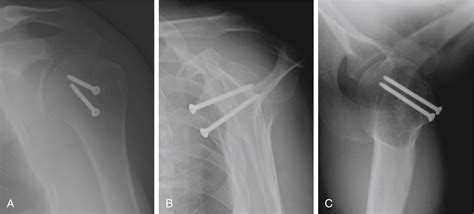

• Arthroscopic Surgery: Minimally invasive surgery to repair the fracture and stabilize the shoulder joint.

• Open Surgery: More invasive procedure to address severe fractures or complex injuries.

• Bone Grafting: In some cases, bone grafting may be necessary to fill the defect caused by the fracture.